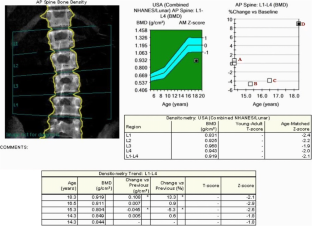

Fig. 1